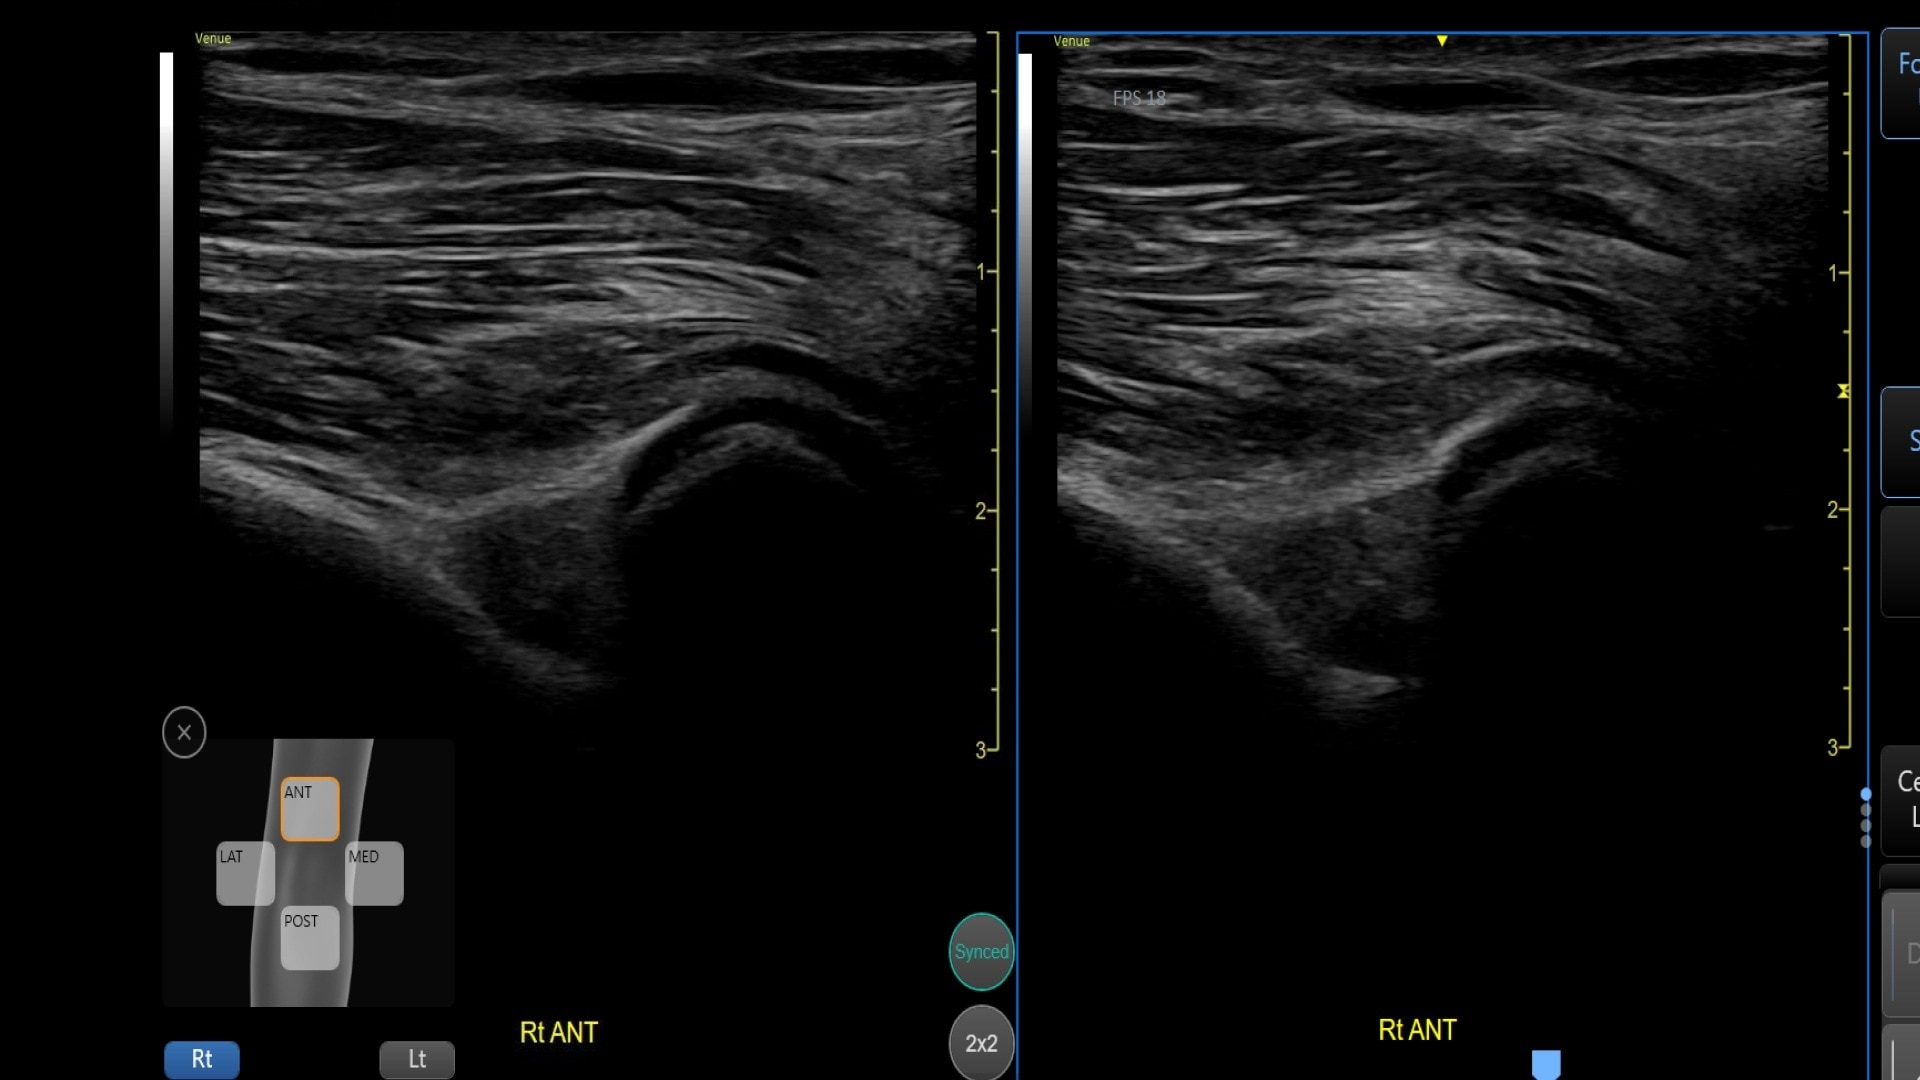

Automatically recall parameter settings with Follow Up

Delivering consistent and clear conclusions for repeated exams on the same patient, Follow Up automatically recalls parameter settings from a previous exam including comments and body patterns. It also supports monitoring of patient response to treatment over time, allowing a side-by-side view of historical and new images.